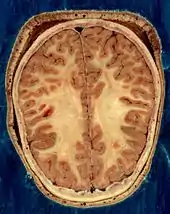

يُغطي المخ وجذع الدماغ والمخيخ، والحبل الشوكي بثلاثة أغشية تُسمى السحايا.منها غشاء الأم الجافية والأم العنكبوتية الغشاء الوسطي والأم الحنون رقيقة جدًا والأكثر حساسية.[17] بين الأم العنكبوتية والأم الحنونة يوجد حيز تحت العنكبوتية وخزانات تحت العنكبوتية، التي تحتوي على السائل الدماغي الشوكي. الغشاء الخارجي للقشرة الدماغية هو الغشاء القاعدي للأم الحنون المسمّى بالدبق المُحدد [الإنجليزية]، وهو جزء مهم من الحاجز الدموي الدماغي،[18] إن الدماغ الحي رخو للغاية وله قوام شبيه بالهلام مشابه للتوفو الطري.[19] تُشكِّل الطبقات القشرية للعصبونات جزءًا كبيرًا من المادة الرمادية في الدماغ، في حين تشكِّل المناطق تحت القشرية الاعمق من المحاور العصبية المادة البيضاء.[20] تشكِّل المادة البيضاء في الدماغ حوالي نصف الحجم الكلي الدماغ.[21]

تُشكِّل القشرة المُخية الجزء الخارجي من المخ، وهي تتكون من مادة رمادية مُرتبة على شكل طبقات. يبلغ سُمكها من 2 إلى 4 ملليمتر (0.079 إلى 0.157 بوصة)، تكون ملتففةٌ وملتويةٌ مِمَّا يُضفي عليها مظهرًا معقدًا.[26] وتحت القشرة توجد المادة البيضاء.الجزء الأكبر من القشرة المخية هو القشرة الحديثة، التي تحتوي على ستة طبقات عصبية. أما ما تبقى من القشرة فهو للقشرة العريقة، والتي تتكون من ثلاث أو أربع طبقات.[27] يتم تعيينالقشرة عن طريق تقسيمات تصل إلى حوالي خمسين مجالًا وظيفيًا مختلفًا تُعرف باسم باحات برودمان. تختلف هذه المناطق بشكل واضح عند رؤيتها تحت المجهر.[28] وتنقسم القشرة إلى منطقتين وظيفيتين رئيسيتين، القشرة الحركية والقشرة الحسية [الإنجليزية].[29] تحتل القشرة الحركية الأولية التي ترسل المحاور إلى الخلايا العصبية الحركية في جذع الدماغ والحبل الشوكي، الجزء الخلفي من الفص الجبهي، مُباشرةً أمام منطقة الغشاء. في المناطق الحسية الأولية [الإنجليزية] تستقبل الإشارات من الأعصاب الحسية والسبيل العصبي عن طريق النوى المهادية [الإنجليزية] في المهاد. وتشمل المناطق الحسية الأولية في القشرة البصرية في الفص القذالي، والقشرة السمعية في أجزاء من الفص الصدغي والقشرة الجزيرية والقشرة الحسية الجسدية [الإنجليزية] في الفص الجداري. الأجزاء المتبقية من القشرة تُسمى بالبَاحاتٌ الترابُطِيَّة. تتلقى هذه المناطق المدخلات من المناطق الحسية والأجزاء السفلى من الدماغ وتشارك في العمليات المعرفية المعقدة مثل الإدراك والتفكير واتخاذ القرارات.[30] تتمثل الوظائف الرئيسية للفص الجبهي في التحكم في الانتباه والتفكير المجرد والسلوك ومهام حل المشكلات وردود الفعل الجسدية والشخصية.[31][32] الفص القذالي هو أصغر فص. وتتمثل وظائفه الرئيسية في الاستقبال البصري والمعالجة البصرية المكانية والحركة والتعرف على الألوان.[31][32] يوجد الفُصيّص القذالي الأصغر في الفص المعروف باسم الإِسْفين [الإنجليزية]. يتحكم الفص الصدغي الذكريات السمعية والبصرية، اللغة والسمع والكلام.[31]